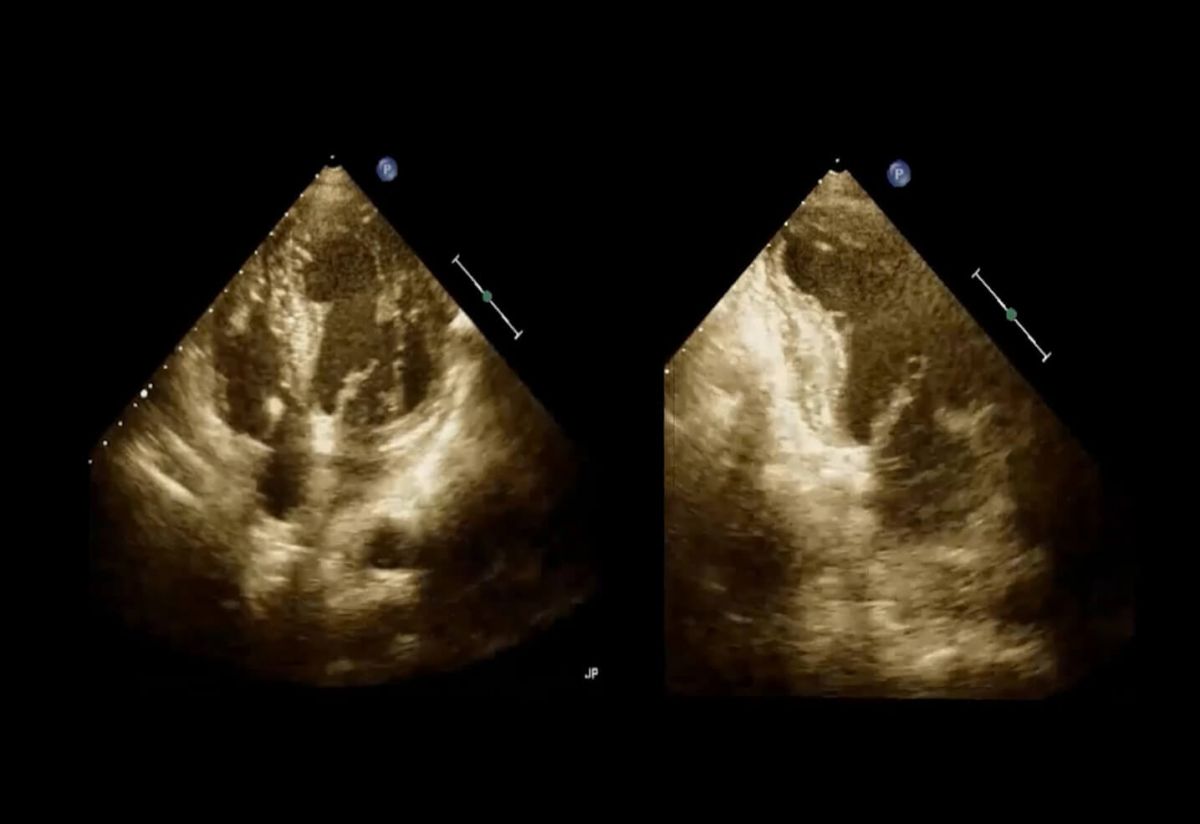

- Fałszywy koniuszek – mechanizm powstawania.

- Uzyskanie właściwego obrazu echokardiografii.

- „Ścinanie” – kiedy się przydaje, kiedy szkodzi?

- Jak unikać zjawiska fałszywego koniuszka?

Uzyskiwanie prawidłowych projekcji koniuszkowych.